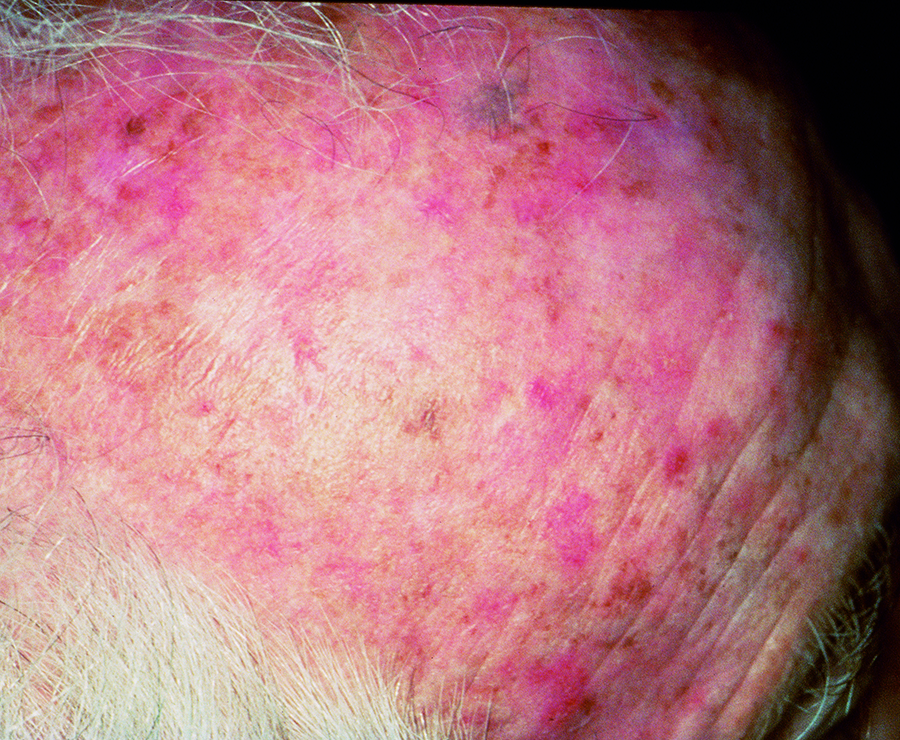

Actinic Keratosis (AK) Photos

Actinic keratosis on head or neck. Photo: International Skin Imaging Collaboration at isic-archive.com